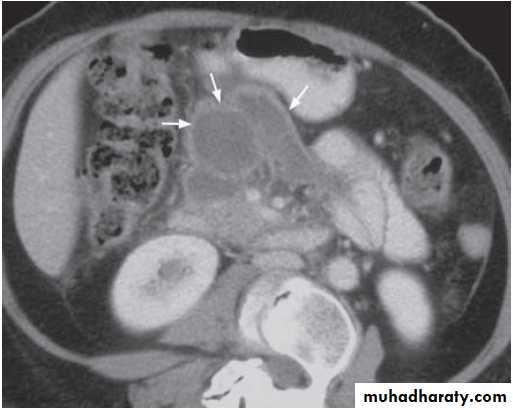

Contrast enhanced axial computed tomography (CT) shows a pancreatic abscess (arrows) appearing as a multiple loculated hypodense lesion with a thick enhancing wall.